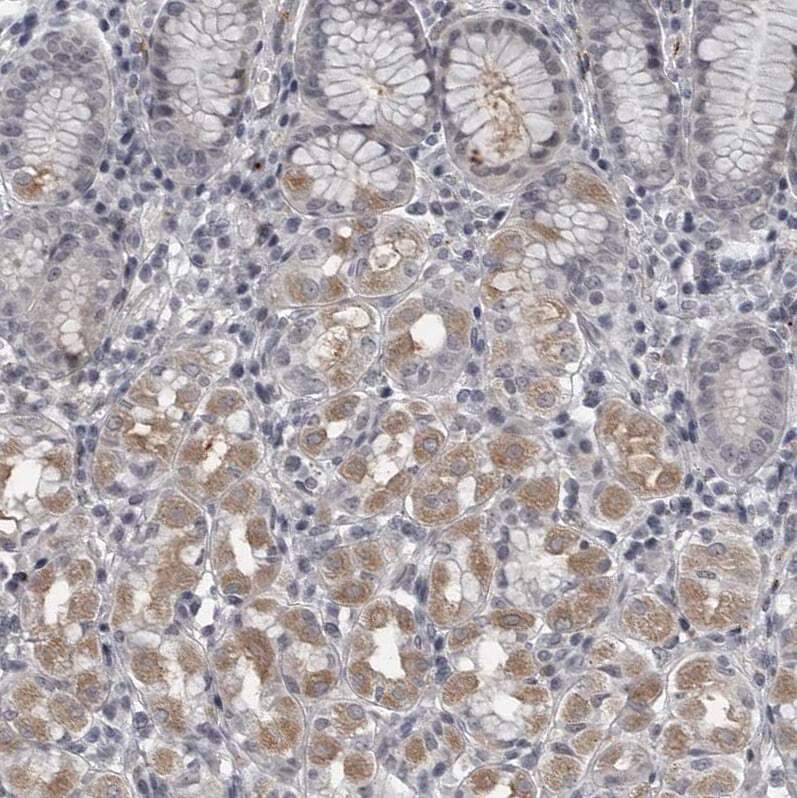

- Immunohistochemical analysis of LYSMD1 in human upper dodenum using LYSMD1 Polyclonal Antibody (Product # PA5-55755) shows weak cytoplasmic positivity in glandular cells.